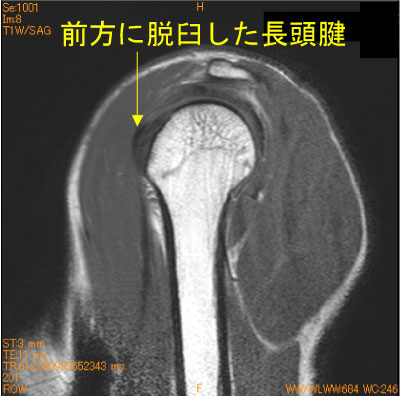

長頭腱前方脱臼-肩関節MRI-

40代男性。20年間のブレークダンス歴(+)。

ダンス時の痛み。結節間溝の横靭帯損傷があり、長頭腱が内側前方に脱臼している。

腱板ばかり見ていると見落とす。

![]() Obl. Sag T1WI |